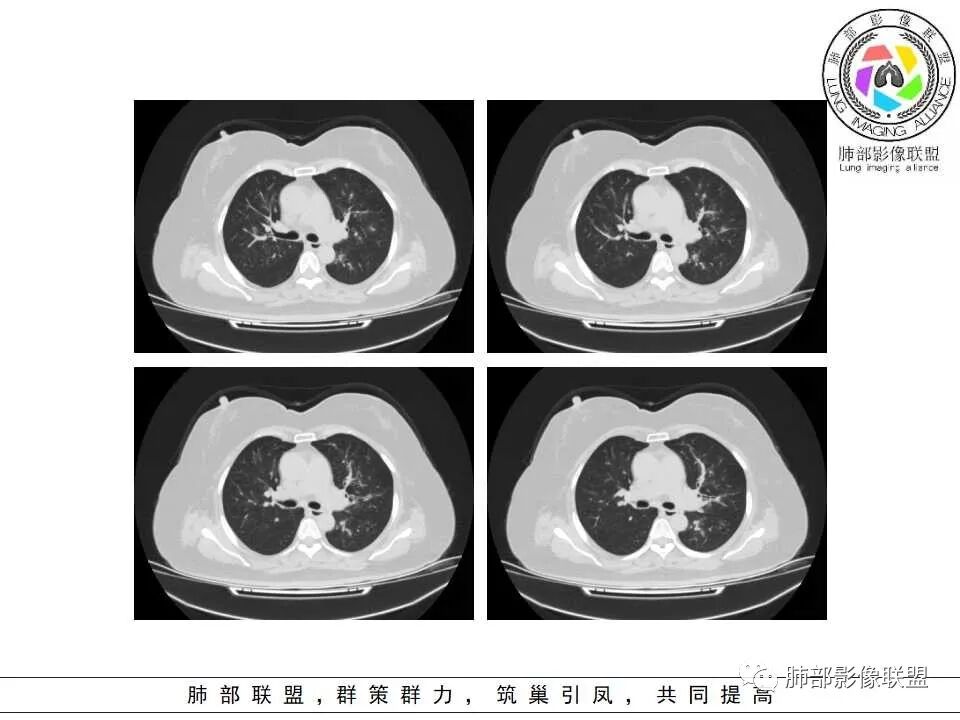

病史+支气管壁增厚+支气管肺炎影像病理基础的苏联红色革命+气喘=气道侵袭性曲霉

弥漫性支气管壁增厚,结合气管镜及痰鸣音,考虑气道曲霉

慢性病程,双肺支气管管壁增厚,周围可见多发点片状高密度影,边缘模糊不清,考虑气道侵袭性曲霉菌病

两肺支气管管壁增厚,沿支气管斑点状及斑片状高密度影,边缘模糊,考虑气道侵袭性曲霉菌,鉴别金葡萄、铜绿

居住地长年潮湿,老年女性,两肺支气管管壁增厚明显,考虑气道侵袭性曲霉菌,鉴别结核。

沿支气管血管束走形,气道壁增厚,边缘模糊,考虑考虑气道侵袭性曲霉,鉴别淋巴瘤。

中老年女性,气道分布的病变,有树芽树雾征,有支气管粘液栓,还有支气管壁增厚,考虑感染性病变,ABBA可能性大,鉴别支原体及军团,支原体以小孩多见,症状轻影像重,发病年龄及影像都不符合,患者住一楼,开麻将馆有聚集性,场地潮湿,不能排除军团肺炎!综合考虑ABBA,不排除军团

双肺沿支气管束见多发斑片状高密度影,界不清,支气管壁增厚,糖尿病史+环境因素,考虑IPA

双肺支气管血管束增粗,边缘模糊呈晕状,沿中轴间质走行分布多发斑片状影,边缘模糊,糖尿病人,血象高,G实验高,气道侵袭为主,考虑曲霉菌感染,鉴别金葡

支气管来源,支气管壁增厚,树芽

糖尿病,血糖控制不好,气促,炎症反应明显(白细胞,crp明显升高,Gm(+)。气道分布的结节磨玻璃密度影,树芽,气管壁增厚。曲霉的可能最大

1.病灶沿支气管分布的特点相当明显,相应支气管壁广泛增厚。这种与支气管关系极为密切的片影和/或结节影,常高度提示气道相关感染,如支气管肺炎。

2.患者两肺多发病变,具有广泛性。如此广泛分布更多见于免疫低下的机会性感染。

3.支气管壁广泛增厚对气道侵袭性曲霉病具有一定的提示意义。注意患者没有支气管扩张,临床也未提供IGE等实验室资料。

1.器官支气管管套样壁增厚和/或支气管扩张,注意壁增厚较均匀,和/或伴有播散性小片影及结节影,注意这些小片影或结节影边界有时较普通炎性病灶清楚。